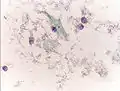

Micrograph of a Pap test showing a low-grade intraepithelial lesion (LSIL) and benign endocervical mucosa. Pap stain. Micrograph of a Pap test showing trichomoniasis. Trichomonas organism seen in the upper right. Pap stain.

Micrograph of a Pap test showing trichomoniasis. Trichomonas organism seen in the upper right. Pap stain.